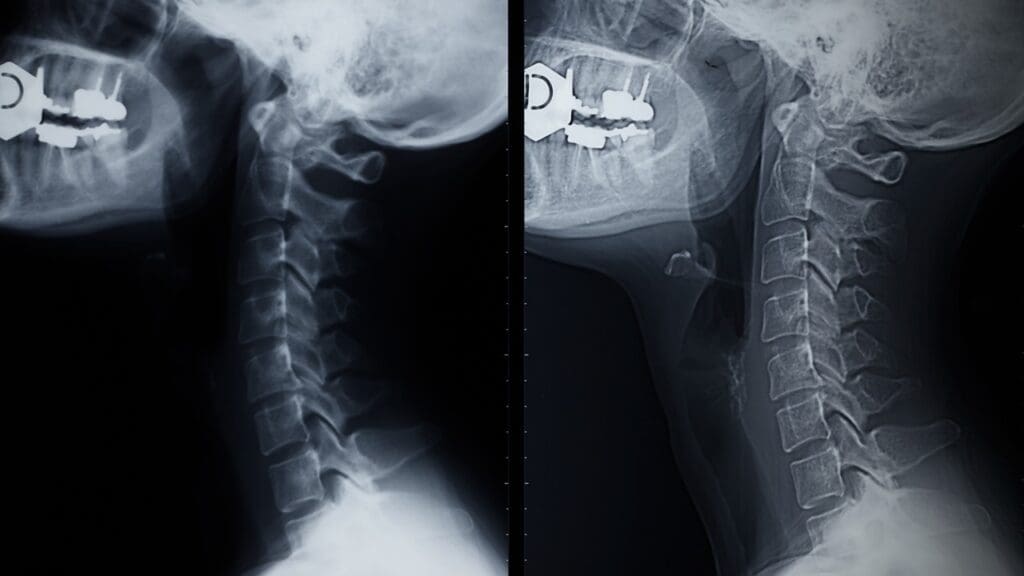

Before ACDF surgery, several tests are done. These include X-rays, MRI, or CT scans to see the spine clearly. Patients might also need to stop certain medicines that could affect the surgery or recovery.

The ACDF procedure uses an anterior approach. This means the surgery is done through a small incision at the front of the neck. This method is chosen because it harms the neck muscles less and lowers post-operative pain.

This approach lets surgeons easily reach the damaged disc. They can then remove it and replace it with a bone graft or implant.

The surgery has several precise steps. First, the damaged disc is carefully taken out. Then, a bone graft or implant is put in to help the bones fuse.

The surgery is done with great care and precision. This helps reduce risks and ensures a successful fusion.